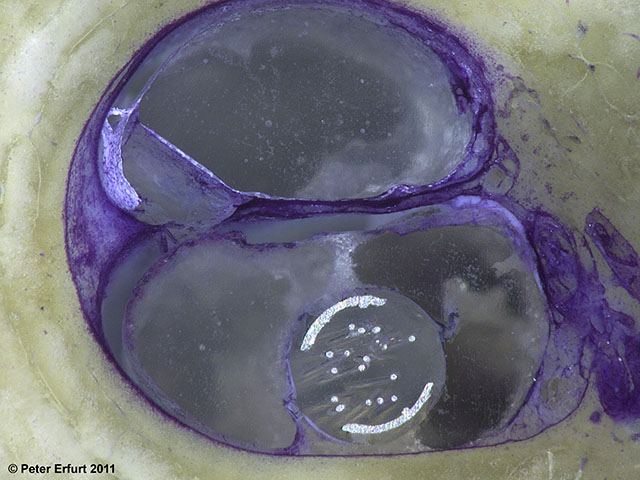

Die Prototypen werden im Rahmen einer simulierten Operation in die Cochlea implantiert. Hier werden Chirurgen in den notwendigen Anpassungen der Operationstechniken geschult und das Verhalten der Elektroden bewertet. Bei der anschließenden histologischen Untersuchung der präparierten Proben ermöglicht der Einsatz der Hartschlifftechnik, die Position der Elektroden und mögliche Schadensprofile – unter zusätzlicher Verwendung radiologischer Bildgebungsverfahren (DVT, µ-CT) – deutlich darzustellen und zu bewerten. Die Ergebnisse fließen direkt in die Optimierung der Prototypen ein.